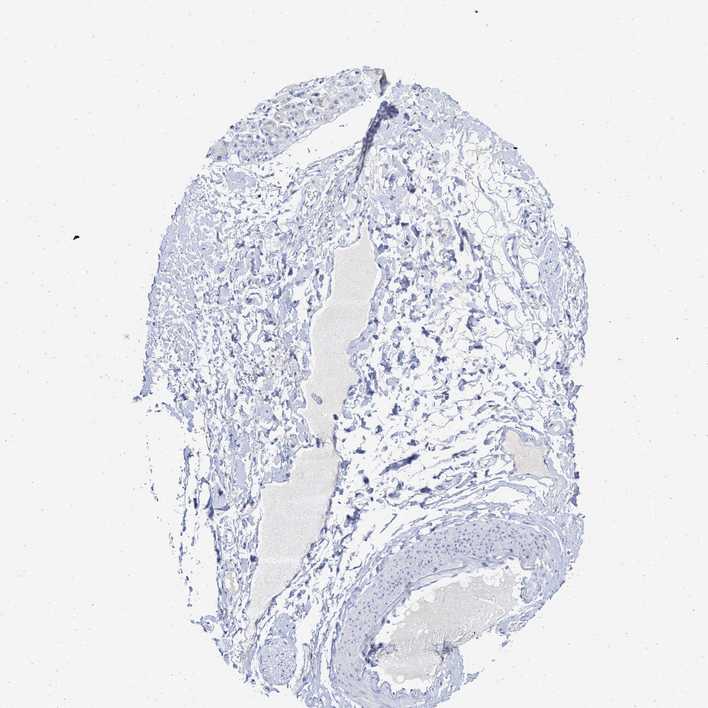

SOFT TISSUE 1 - Antibody stainingi

Antibody staining in the annotated cell types in the current human tissue is reported as not detected, low, medium, or high, based on conventional immunohistochemistry profiling in selected tissues. This score is based on the combination of the staining intensity and fraction of stained cells.

Each image is clickable and will lead to virtual microscopy that enables deeper exploration of all samples and also displays staining intensity scores, fraction scores and subcellular localization as well as patient and tissue information for each sample.

Antibody HPA016816Antibody HPA017382

Chondrocytes -Not detected

Fibroblasts Not detectedNot detected

Peripheral nerve Not detectedNot detected